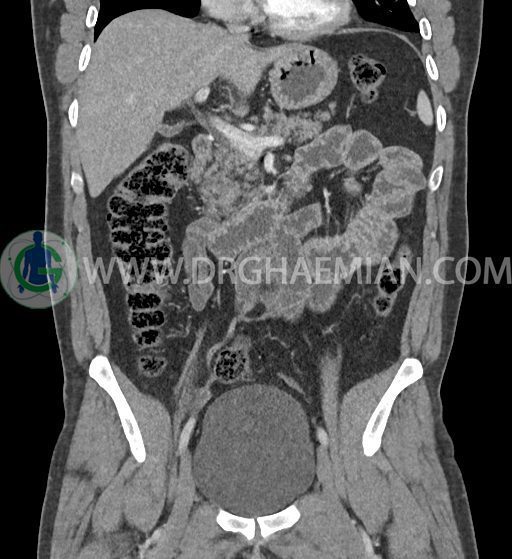

در سی تی اسکن اسپیرال شکم و لگن با کنتراست خوراکی و وریدی (مولتی دیدکتور 16 با مقاطع ظریف و بازسازی های ساژیتال و کرونال) :

ضایعه ای در معده ، روده باریک و کولون مشهود نیست .

مایع آزاد در حفره شکم و لگن رویت نمی شود.